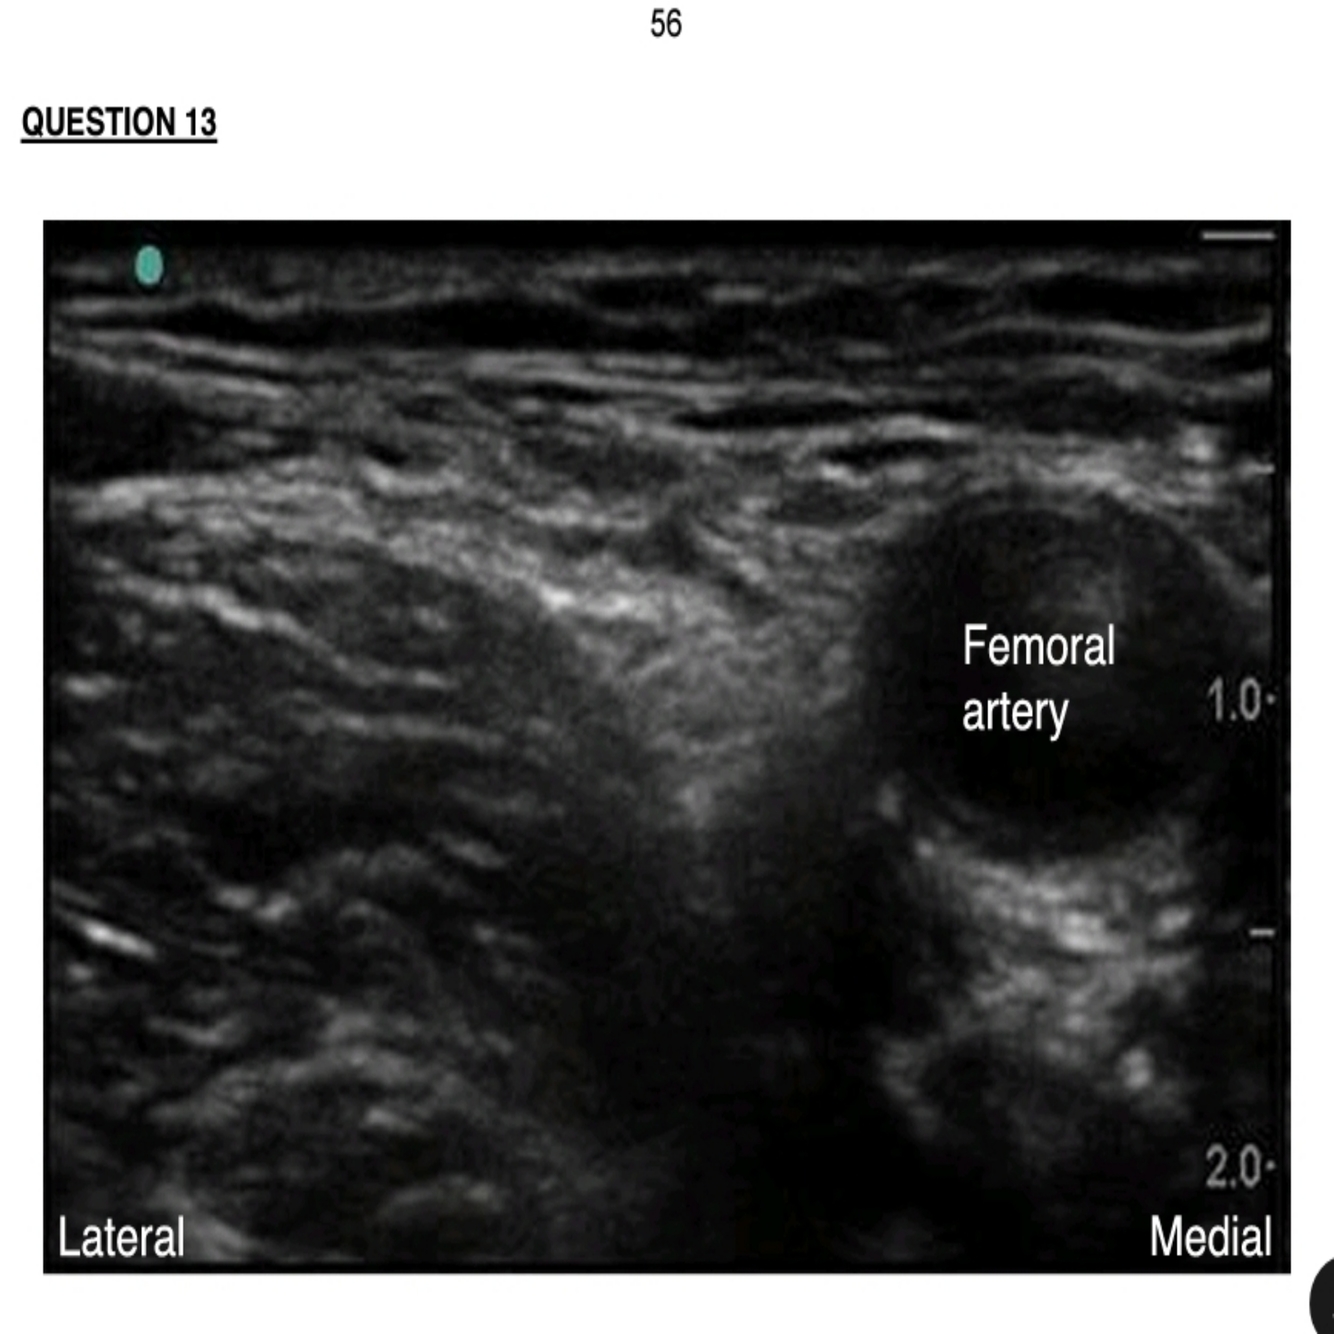

Q

a) Above is an ultrasound image in the transverse plane just caudal to the inguinal ligament showing normal anatomy. Draw a diagram of this image indicating the important venous, neural and fascial structures.

57 What is the importance of identifying the fascia layers when doing nerve blocks in this region? (2)

List six methods to prevent nerve injury during nerve blocks.